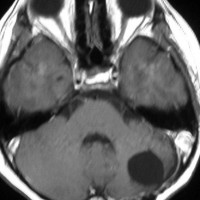

- 境界がはっきりした腫瘍です,くりんとしています

- ガドリニウム造影剤で白く映ります(増強される)

- でも,ガドリニウム造影剤が入らなくて白く映らないものもあります

- 周囲の小脳が腫れることが多いです(脳浮腫)

- CTでは石灰化がみられることがあります

- CTでは小脳より白っぽい灰色(高密度)に写ります

- 他の腫瘍との鑑別は,第4脳室腫瘍のところを読んでみてください

単純CTでは,腫瘍は比較的境界明瞭で石灰化も高頻度に認められます。充実性腫瘍であることが多いのですが,のう胞あるいは壊死形成も見られます。細胞密度が高い腫瘍であるのでCT等吸収域もしくは高吸収域として描出され,造影剤では均一に強く増強されます。MRIでは,T1強調画像で低信号域として描出され,T2強調画像で等信号から高信号を呈すします。ガドリニウム増強効果は症例により様々であり,強い均一な増強効果を示す例から,ほとんど増強されない症例まであります。髄液播種の頻度が高いので,全脳脊髄にわたるMRI検査が必須です。また,MRIで髄腔転移が認められなくとも髄液細胞診で陽性となることがあるので,もしできれば腰椎穿刺あるいは脳室内髄液によって細胞診を行います。